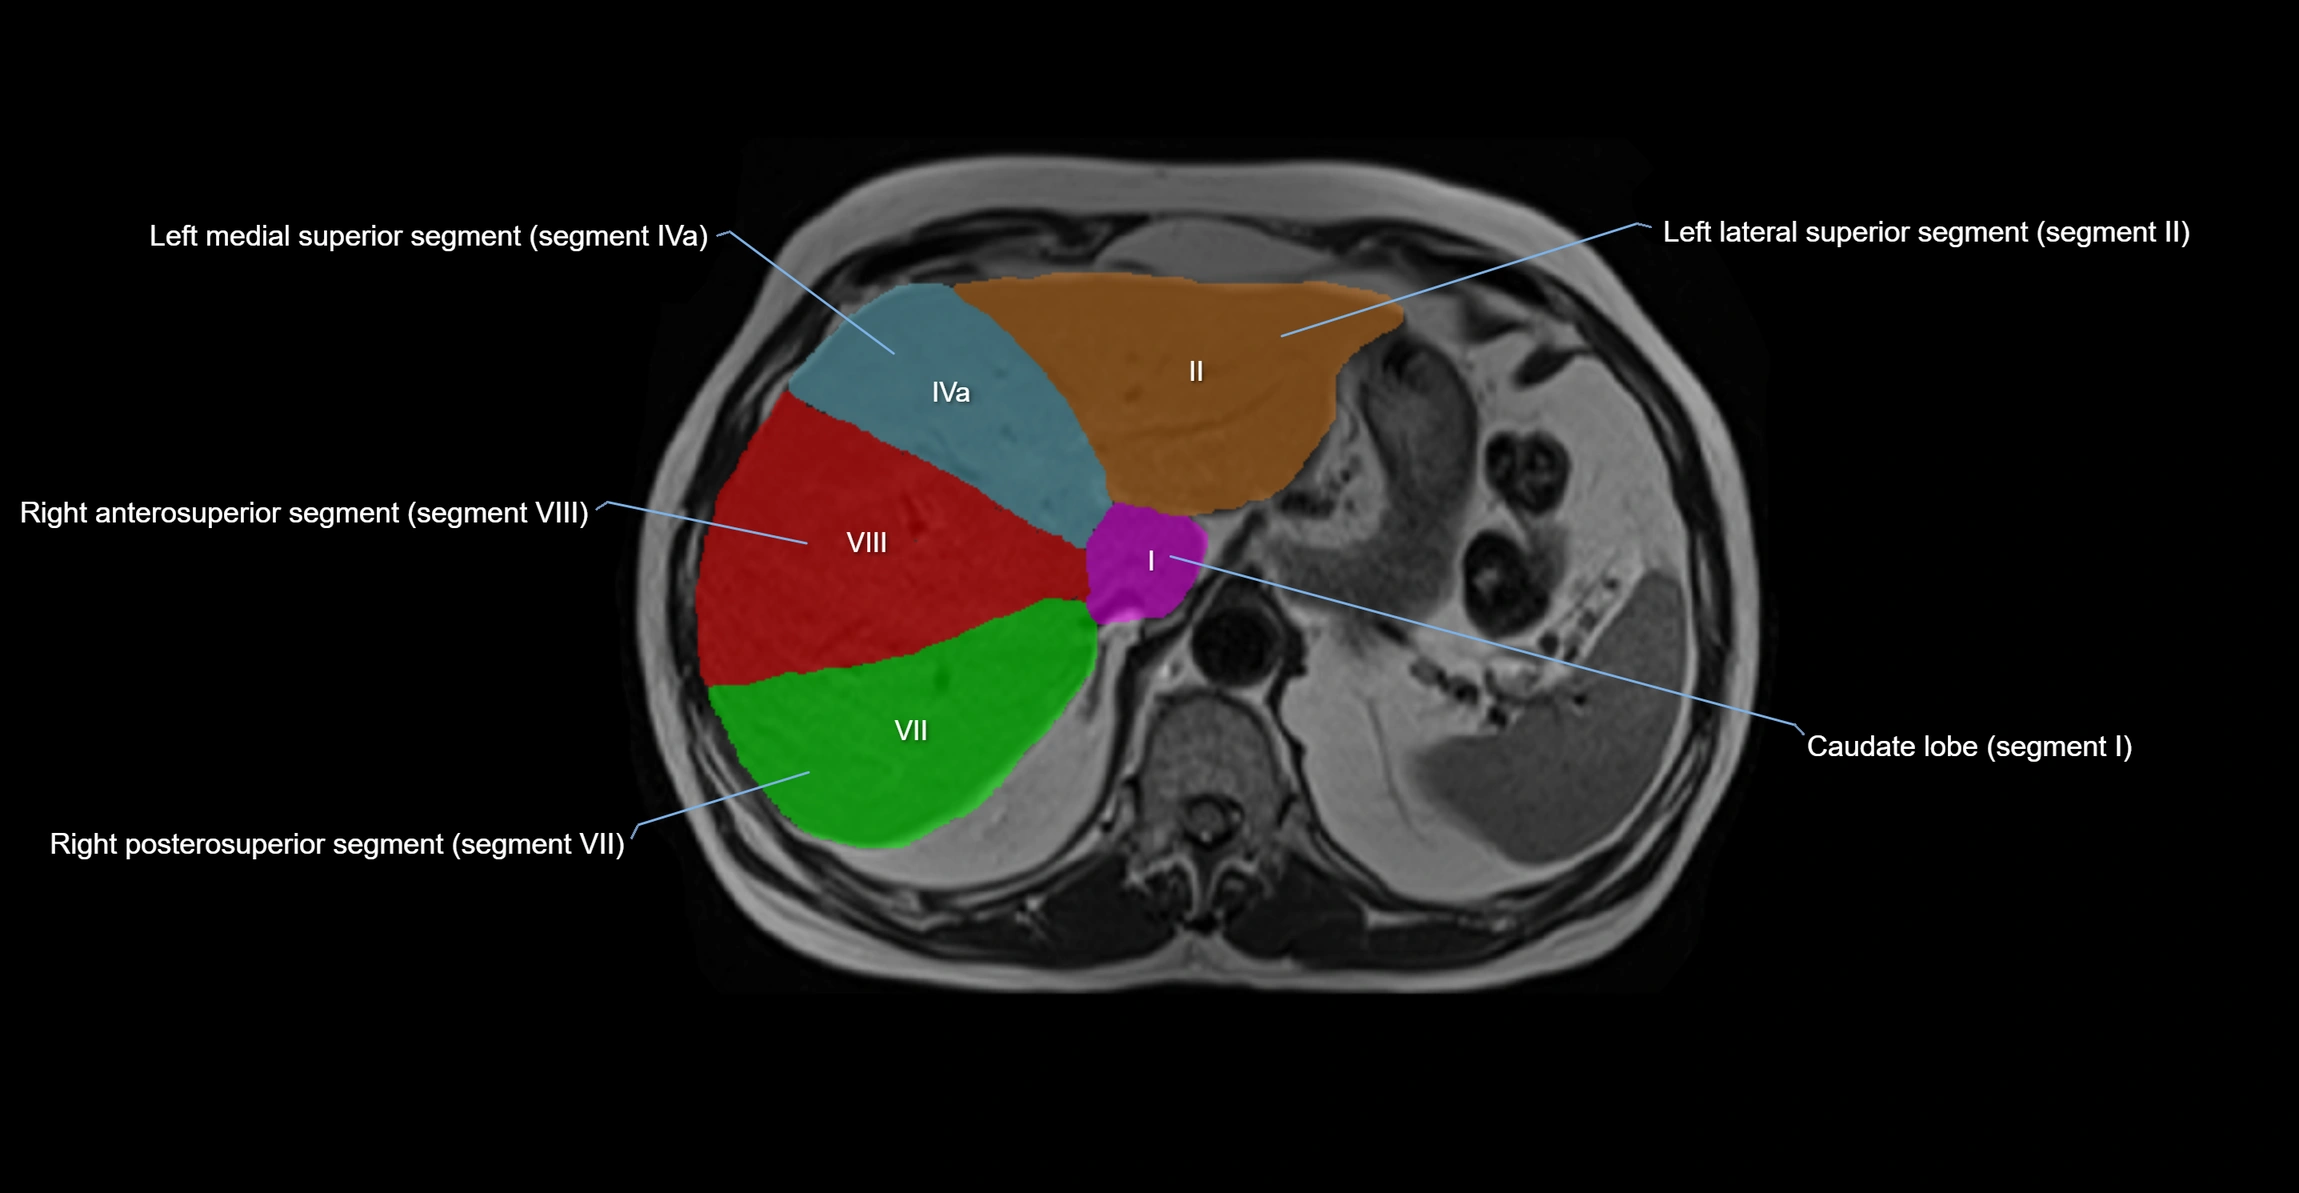

The caudate lobe of the liver is a distinct anatomical subdivision of the liver, designated as segment I in Couinaud’s classification. It lies on the posterior surface of the liver, between the fissure for the ligamentum venosum (left boundary) and the groove for the inferior vena cava (IVC) (right boundary). Superiorly, it is related to the posterior liver surface, and inferiorly it is separated from the left lobe by the porta hepatis.

The caudate lobe is unique because it receives dual portal venous and arterial inflow from both the right and left portal veins and hepatic arteries. It also has independent venous drainage directly into the IVC via multiple small hepatic veins, unlike other lobes that drain through the three main hepatic veins.

This anatomical autonomy makes the caudate lobe especially significant in liver surgery, transplantation, and hepatic venous outflow obstruction syndromes (e.g., Budd–Chiari syndrome). Enlargement of the caudate lobe is a characteristic imaging feature in chronic liver disease and cirrhosis.

• Segment I (Couinaud classification)